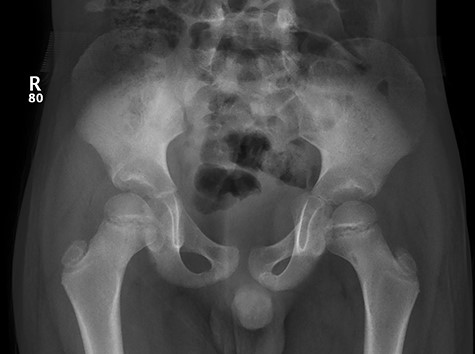

CT hips reported a well-defined lesion seen bilaterally in the neck of femur anterior infero-medial aspect, more prominent on the left side measuring 7 x 3 mm on left side both in coronal (Fig. 3) and axial (Fig. 4) views. On the right side, other lesion measuring 2 x 1 mm (Fig. 5) seen in coronal view. These two lesions are well defined with a sclerotic border with a small cortical defect. The lesion shows fat density. The symmetrical appearance of the lesion combined with the fat density and location suggest the diagnosis of synovial herniation pit. MRI Pelvis revealed minimal left hip joint effusion with loculated fluid seen along the trochanteric bursa with the largest measuring 0.9 x 1.5 cm (Fig. 6, 7).

Showed axial cut of CT hips demonstrating the synovial pit on left and right side.

Follow-up X-ray showed regression of the lesion in the form of progression of the dense sclerosis of the defect of the left femur while the right femur neck lesion is barely visible (Figure 10) and advised for watchful waiting.